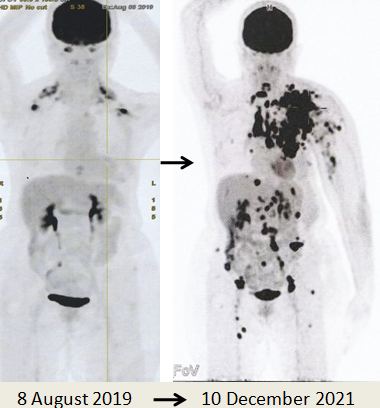

Karena metastasis seperti yang ditunjukkan pada pemindaian PET yang dilakukan pada 10 Desember 2021, Lucy tidak punya pilihan selain melanjutkan kemoterapi. Memang kanker telah menyebar luas.

Bandingkan ketiga gambar ini :

Kiri: Setelah operasi Lucy menjalani terapi alternatif, menolak kemoterapi. Hasilnya adalah metastasis luas (tengah).

Kanan: Lucy tidak punya pilihan selain menjalani kemoterapi. Hasil dari 6 siklus kemoterapi sungguh luar biasa! Selama lebih dari 25 tahun saya berurusan dengan pasien kanker, saya belum pernah melihat hasil kemoterapi yang luar biasa seperti ini. Salut dengan ahli onkologi! Anda menyelamatkan Lucy!

Faktanya, hasil chemo ini sangat sulit dipercaya sehingga orang tergoda untuk bertanya apakah itu asli dan bukan palsu? Jawaban saya TIDAK, studi detail hasil PET scan di bawah ini adalah nyata! Kaji gambar berikut dengan cermat – sebelum dan sesudah kemoterapi.

2. Pada tanggal 8 Agustus 2019, saya berkonsultasi dengan dokter spesialis onkologi di sebuah rumah sakit swasta di Kuala Lumpur. Pemindaian PET dilakukan. Hasilnya menunjukkan:

• Serapan FDG derajat rendah terlihat pada perubahan inflamasi pascaoperasi pada dinding dada anterior kiri. Tidak ada nodus hipermetabolik atau metastasis jauh.